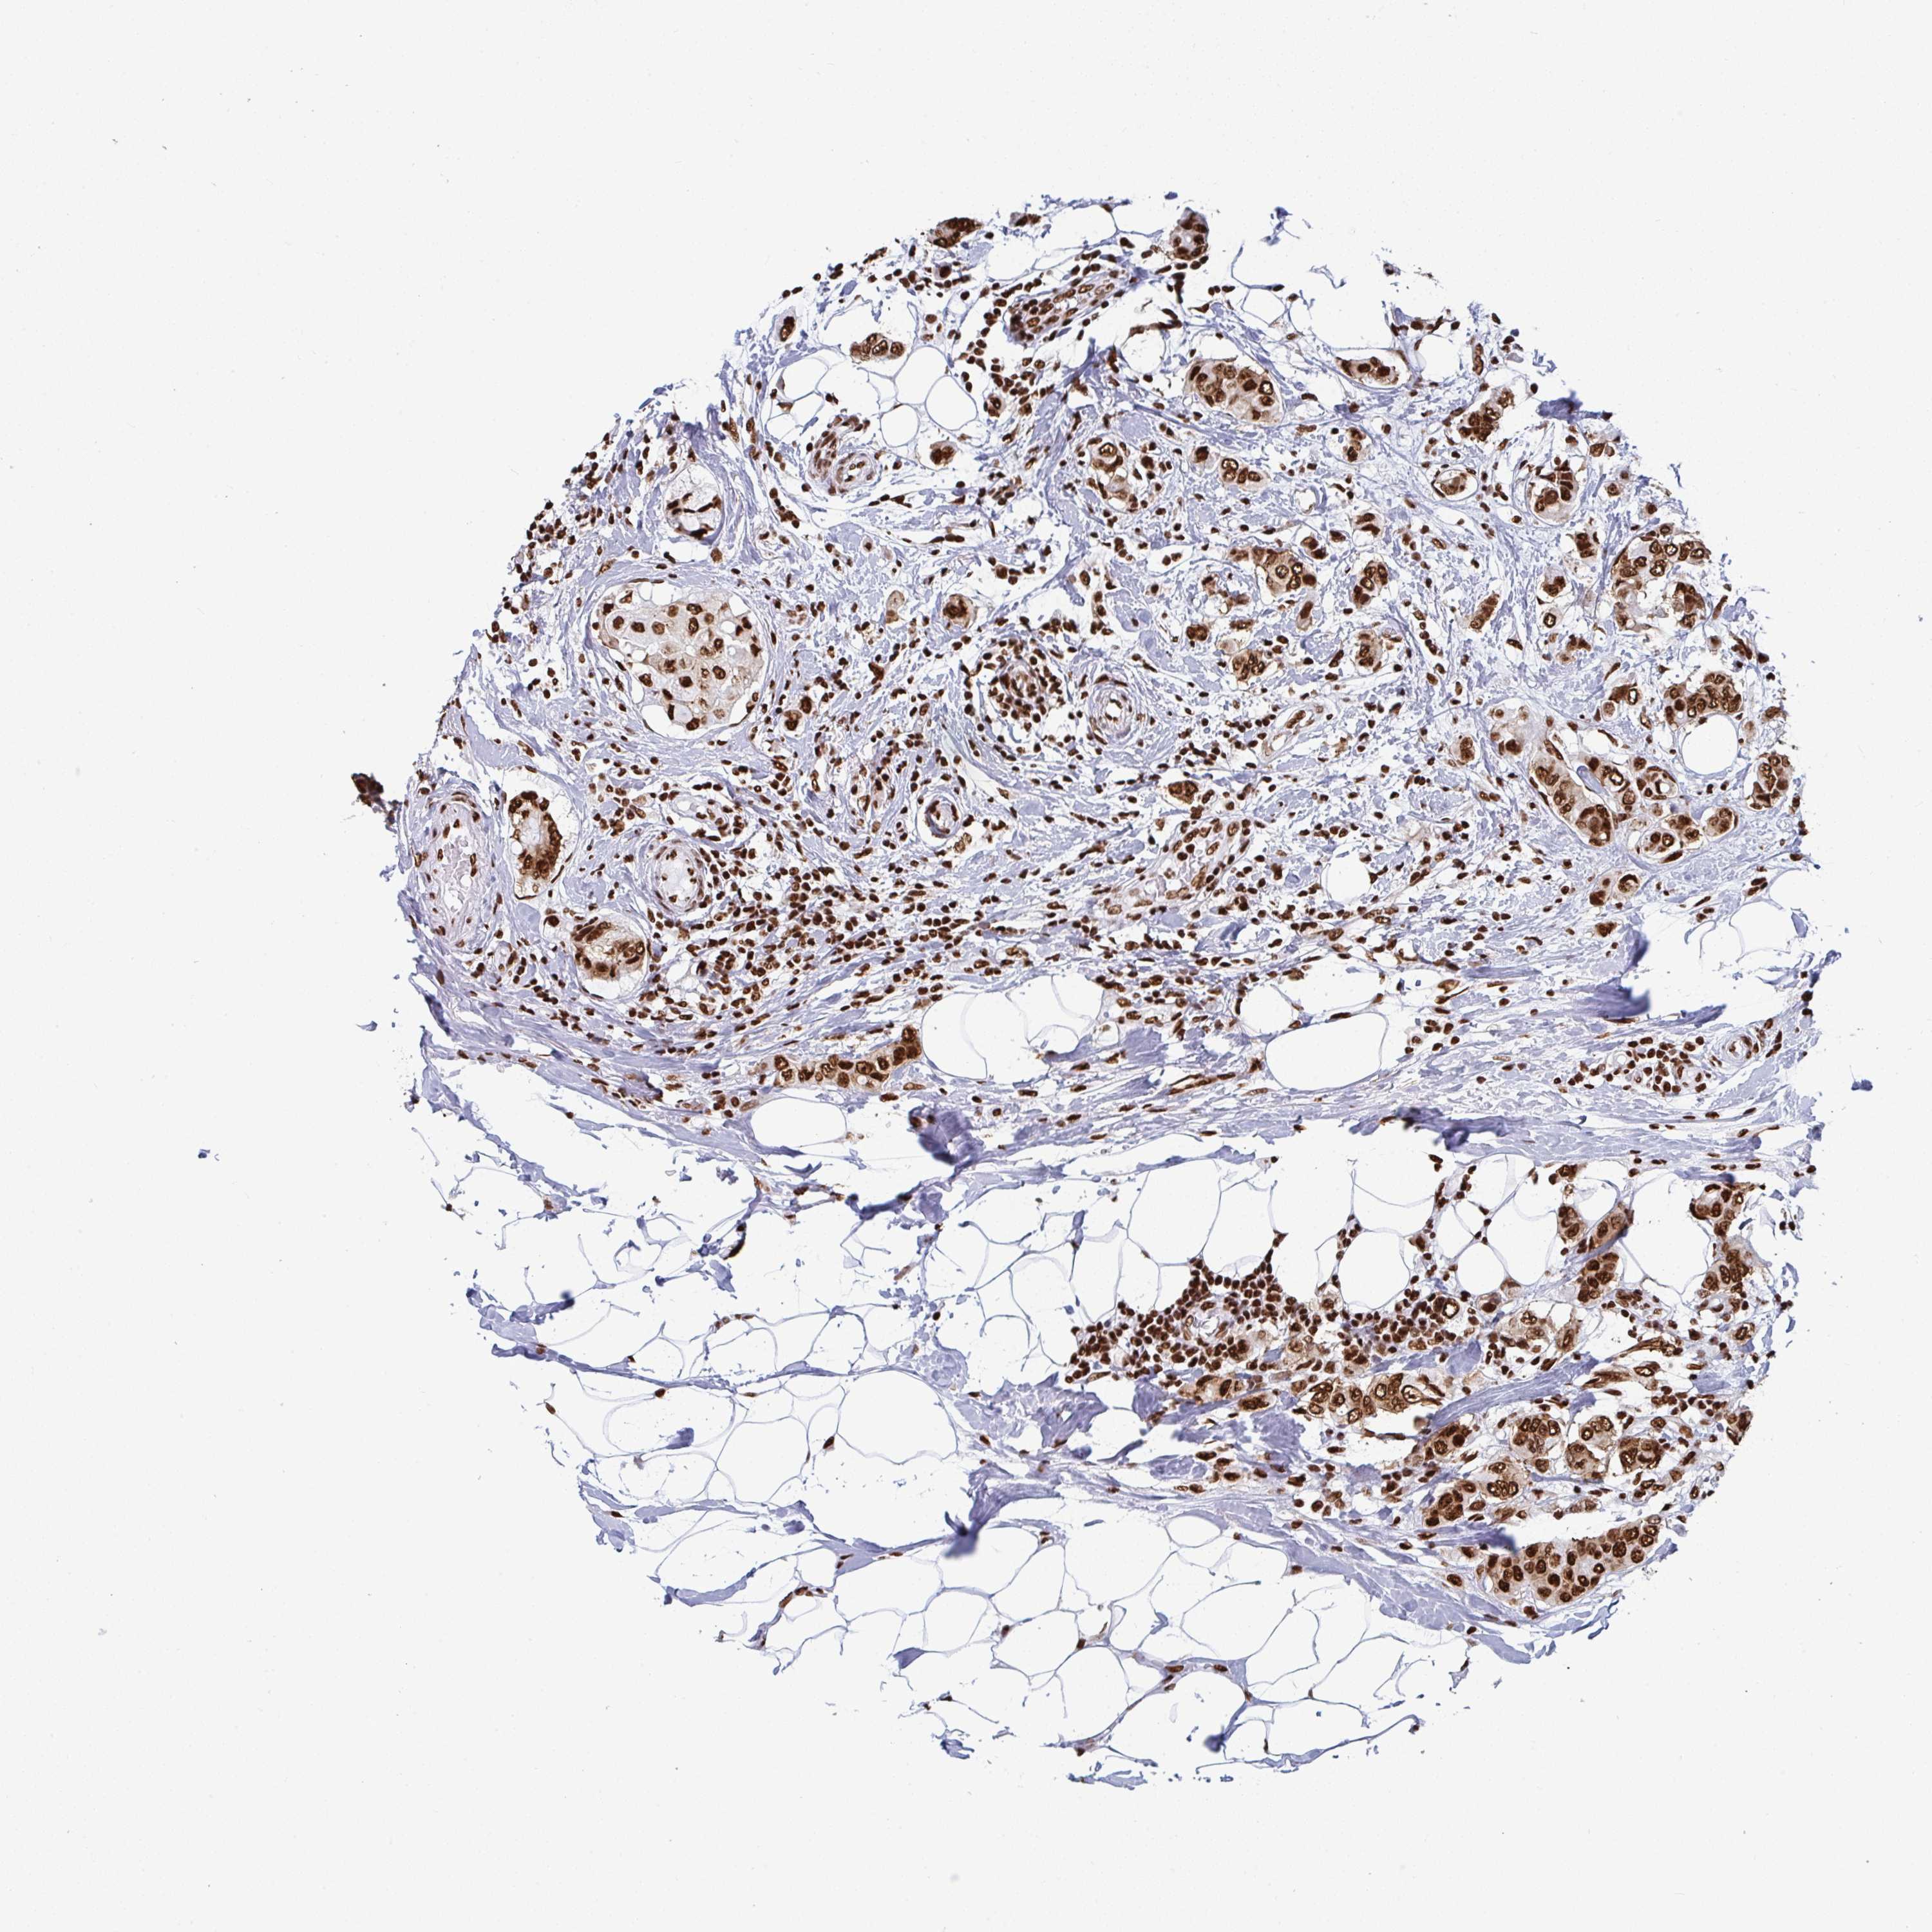

CANCER BREAST CANCER Show tissue menu

BRCA TCGA BRCA VALIDATION PROTEIN EXPRESSION

Breast cancer

Human cancer